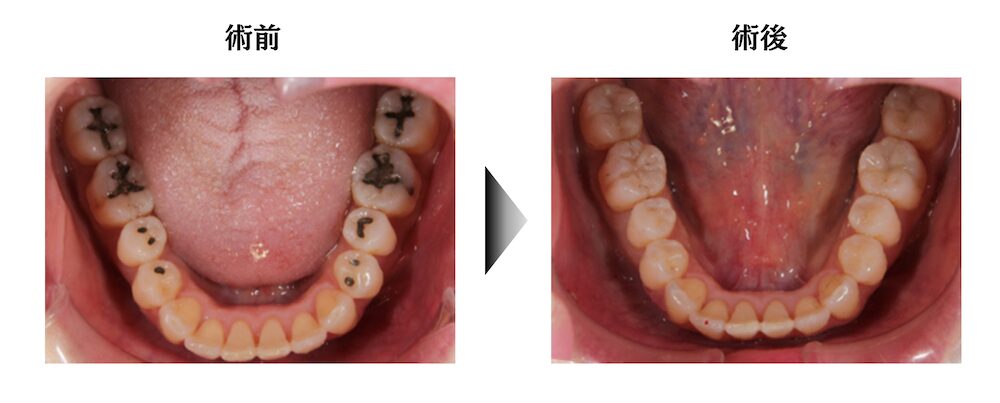

奥歯8本の金属の詰め物をやり直した症例

| 治療内容 | 奥歯のアマルガム(金属)の詰め直し |

| 治療期間 | 治療回数 2回 |

| 治療費用 | ダイレクトボンディング1本4万円 × 8本 |

| リスク | 継時的変色がある場合があります。 |